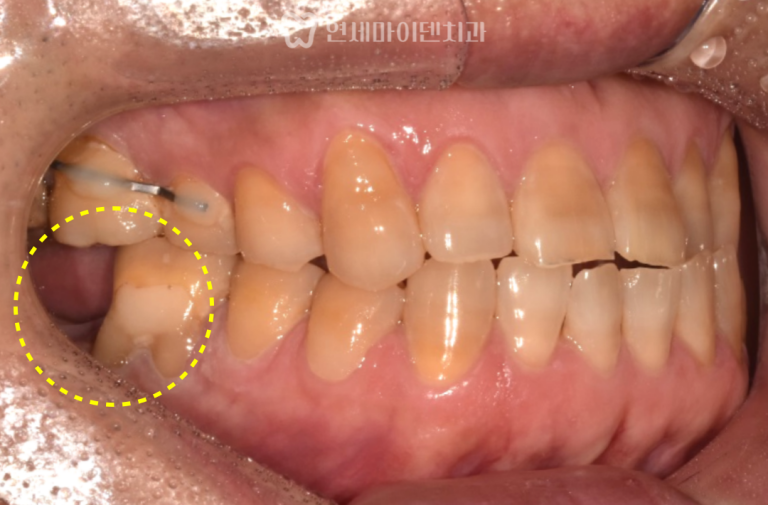

발치 즉시 임플란트 증례: 잇몸여드름, 치근파절

발치 즉시 임플란트 증례: 잇몸여드름, 치근파절 잇몸에서 고름이 반복적으로 올라오거나잇몸이 붓고 가라앉기를 반복하는 경우, 단순한 잇몸…